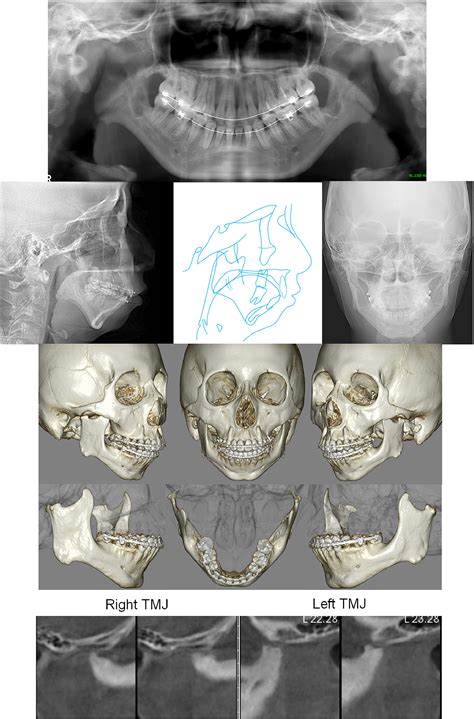

To confirm a diagnosis of Idiopathic Condylar Resorption, specialists use a multi-faceted approach. A physical exam is rarely sufficient; advanced imaging is essential. A Cone Beam Computed Tomography (CBCT) scan is the gold standard for visualizing the condylar heads and determining the extent of bone loss. MRI scans may also be utilized to evaluate the condition of the articular disc within the joint. By comparing serial radiographs over several months, an oral and maxillofacial surgeon can track the rate of resorption to determine if the condition is currently active or stable.